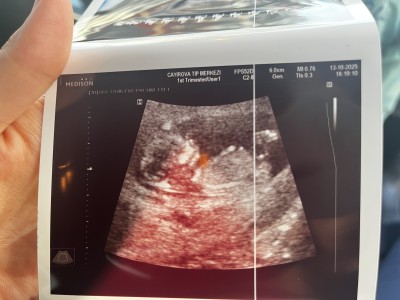

Kızlar 11+

imageKızlar 11+4 teyiz doktor çok erken dedi ama bir tahminim var dedi sizin var mı anlayan varsa yorumlayabilir mi

Gebelik haftası 11+4

İlk fotoda mı öyle hissettin 2. De mi bende ilkte kız ikincide erkeğe benzettim amin inşallah

Yok yapısından baktim daha narin kafası vucuduyla eşit gibi . İkincide de zaten bacak arası görünmüyor ki